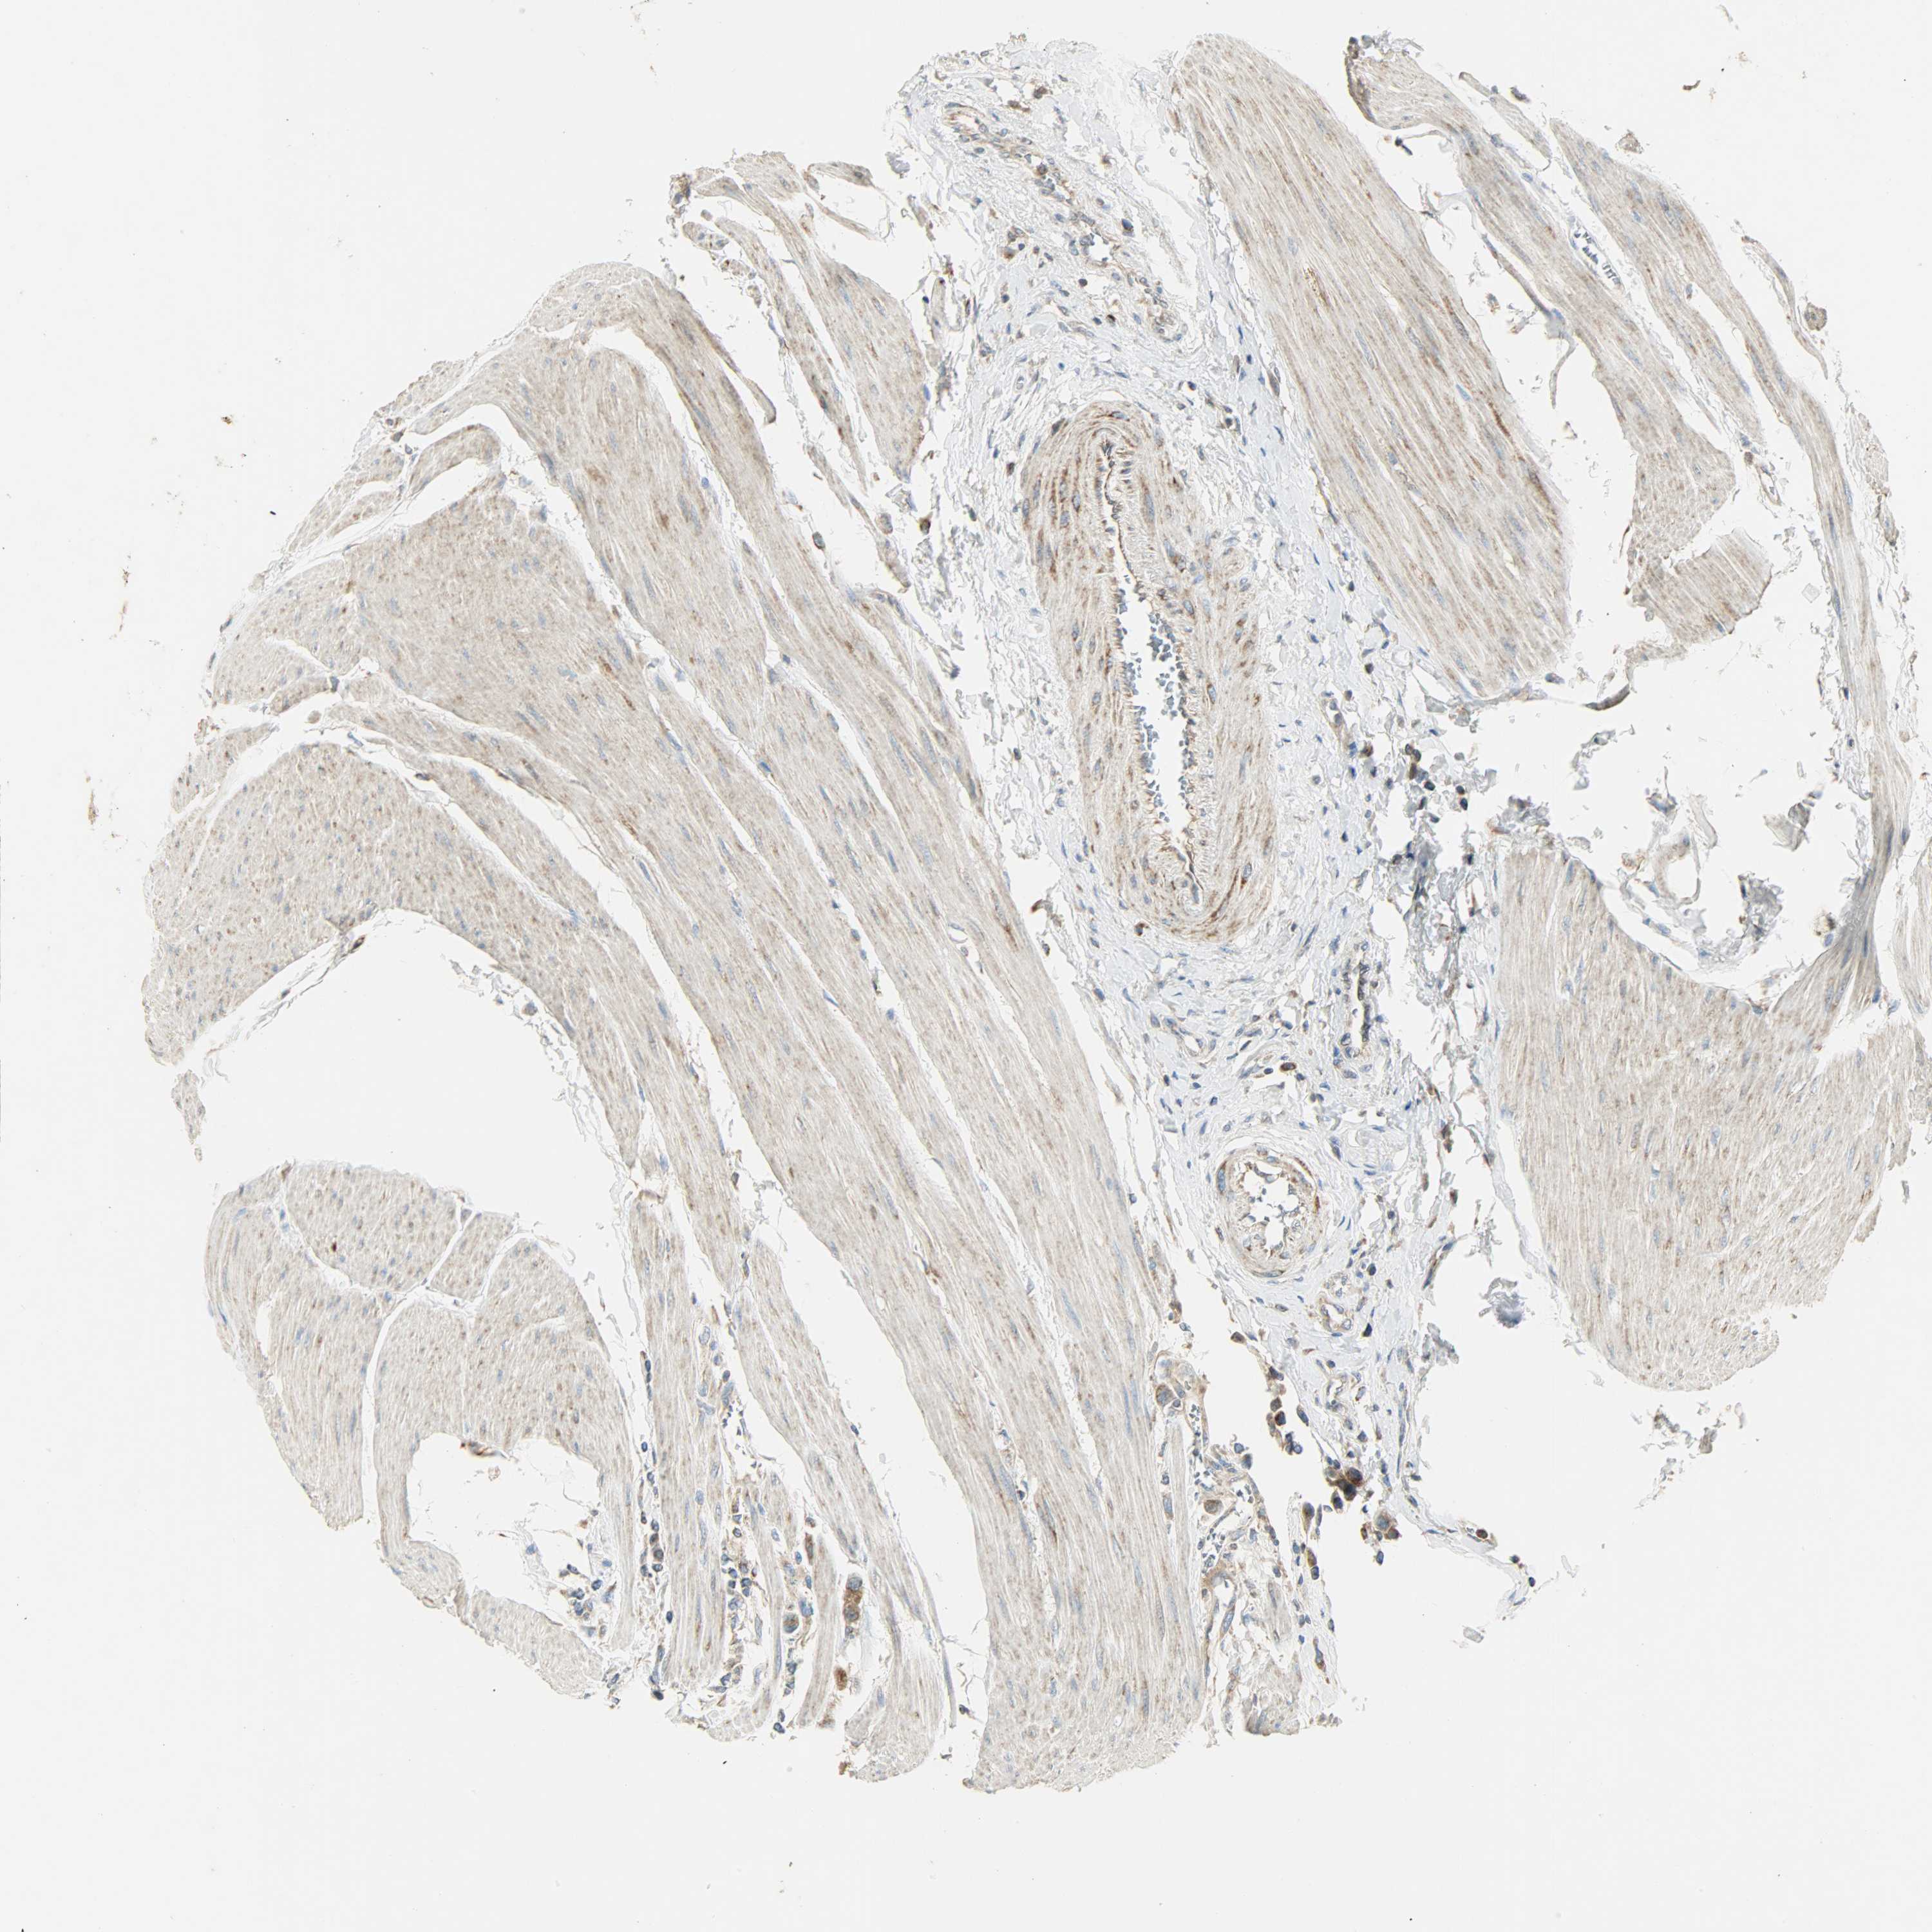

UROTHELIAL CANCER - Protein expressioni

A mouse-over function shows sample information and annotation data. Click on an image to view it in a full screen mode. Samples can be filtered based on level of antibody staining by selecting one or several of the following categories: high, medium, low and not detected. The assay and annotation is described here.

Note that samples used for immunohistochemistry by the Human Protein Atlas do not correspond to samples in the TCGA dataset.

Antibody stainingi

Antibody staining in the annotated cell types in the current human tissue is reported as not detected, low, medium, or high, based on conventional immunohistochemistry profiling in selected tissues. This score is based on the combination of the staining intensity and fraction of stained cells.

Each image is clickable and will lead to virtual microscopy that enables deeper exploration of all samples and also displays staining intensity scores, fraction scores and subcellular localization as well as patient and tissue information for each sample.

Antibody HPA004829

Antibody CAB004975

Urothelial carcinoma, High grade

Urothelial carcinoma, Low grade